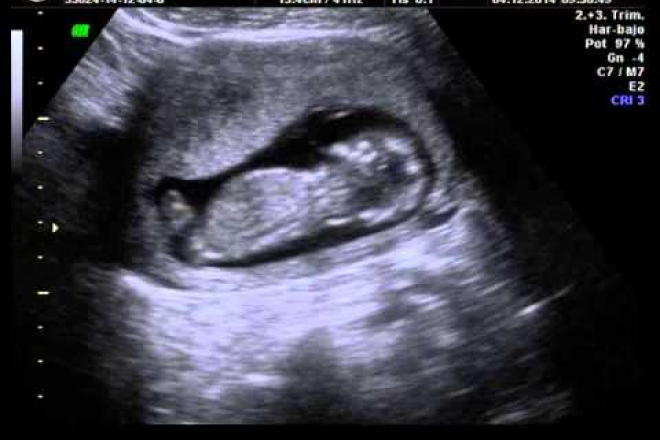

Ultrasonografía en el segundo trimestre:

• Las estructuras fetales ya perfectamente formadas son claramente valorables por la abundancia relativa del líquido amniótico.

• Los datos que se obtienen en el ultrasonido del segundo trimestre están dirigidos a determinar la normalidad estructural del feto, el número de fetos, su vitalidad y la normalidad de las diferentes estructuras anatómicas para descartar malformaciones.

• Se realizan las diferentes mediciones universalmente aprobadas como útiles, tales como el diámetro biparietal, la circunferencia abdominal y la longitud del fémur, así como la proporción entre la cabeza y el tronco del feto.